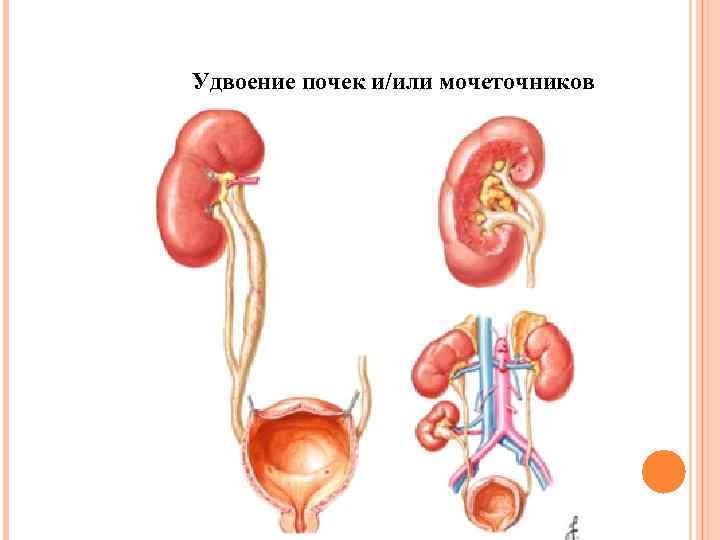

Удвоение почек и/или мочеточников

Удвоение почек и/или мочеточников